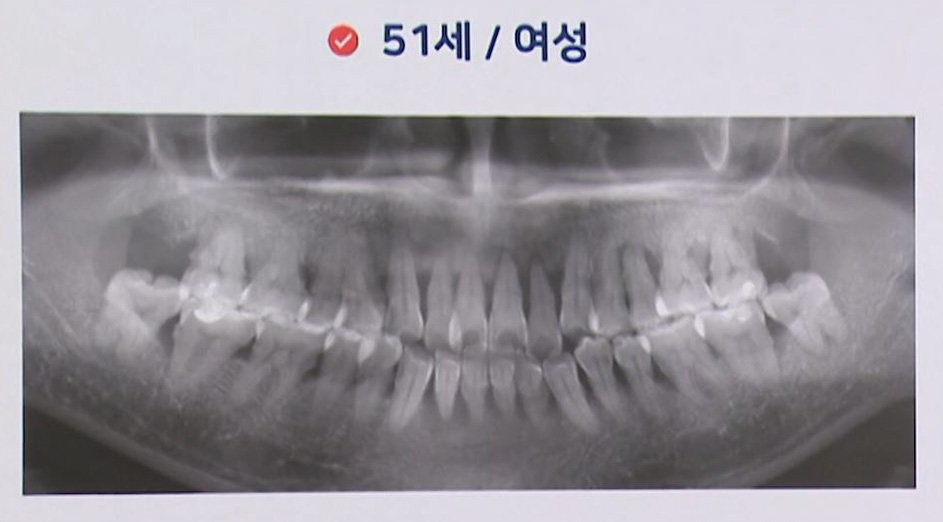

한 분은 아랫니의 공백이 있었고, 앞서 보신 분은요. 지금 보신 분은 위쪽에 이제 치아가 공백이 있습니다.

이분은 치아가 상실된 건 없습니다. 제2 대구치까지 다 있는 경우인데 한꺼번에 빼야 할 치아를 오히려 발치하지 않고 치료를 미루기만 하다 보니까. 우리가 귤 상자에서 귤이 하나 썩어가는데 솎아내지 않고 그냥 있다 보면 그렇죠. 그 곰팡이 균들이 담대로 퍼지듯이, 아까도 말씀드렸지만 각종 많은 박테리아와 세균들. 구강 내에도 곰팡이 균이 있습니다. 푸르스름하게 치석이 끼기도 하거든요. 그래서 이것들이 퍼지는 겁니다, 사실은. 우리가 잘 때는 우리가 그 균에 대항할 수 없잖아요. 그래서 양치도 주무시기 직전에 하는 게 좋고 어쨌든 이런 경우에 치료를 계속 미루다가 발치하게 되면 굉장히 치료 기간이 길어지게 되고.